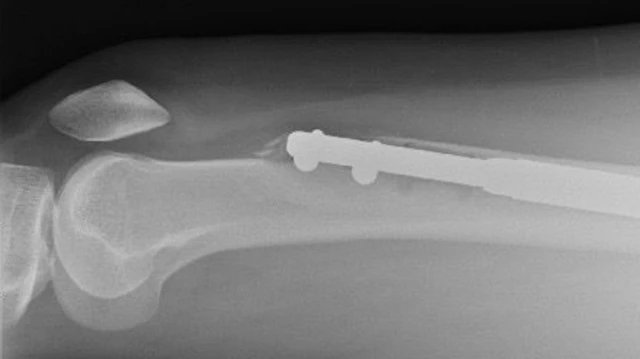

ਇਸ ਪ੍ਰਕਿਰਿਆ ਵਿੱਚ ਥੋੜ੍ਹਾ ਜਿਹਾ ਦਰਦ ਹੁੰਦਾ ਹੈ ਕਿਉਂਕਿ ਲੱਤ ਦੀ ਹੱਡੀ ਨੂੰ ਦੋ ਹਿੱਸਿਆਂ ਵਿੱਚ ਤੋੜ ਕੇ ਉਨ੍ਹਾਂ ਵਿਚਾਲੇ ਧਾਤ ਦੀ ਰਾਡ ਲਗਾਈ ਜਾਂਦੀ ਹੈ।

ਹੌਲੀ-ਹੌਲੀ ਦੋਵਾਂ ਹਿੱਸਿਆਂ ਵਿਚਾਲੇ ਲੱਗੇ ਧਾਤ ਦੇ ਇਸ ਰਾਡ ਦੀ ਲੰਬਾਈ ਵਧਾਈ ਜਾਂਦੀ ਹੈ, ਤਾਂ ਜੋ ਮਰੀਜ਼ ਦੀ ਲੰਬਾਈ ਵਧੇ।

ਅਗਲੇ ਦਿਨ ਜਦੋਂ ਸਕੈਨ ਕੀਤਾ ਗਿਆ ਤਾਂ ਈਲੇਨ ਦਾ ਡਰ ਸਹੀ ਸਾਬਤ ਹੋਇਆ। ਉਨ੍ਹਾਂ ਦੇ ਖੱਬੇ ਪੈਰ ਦੀ ਮੇਖ ਹੱਡੀ ਨੂੰ ਵਿੰਨ੍ਹਦੀ ਹੋਈ ਬਾਹਰ ਆ ਗਈ ਸੀ। ਇਹ ਫੀਮਰ (ਲੱਤ ਦੇ ਉਪਰਲੇ ਹਿੱਸੇ ਦੀ ਹੱਡੀ) ਨੂੰ ਤੋੜ ਕੇ ਬਾਹਰ ਨਿਕਲੀ ਸੀ। ਫੀਮਰ ਸਰੀਰ ਦੀ ਸਭ ਤੋਂ ਮਜ਼ਬੂਤ ਹੱਡੀ ਹੈ।